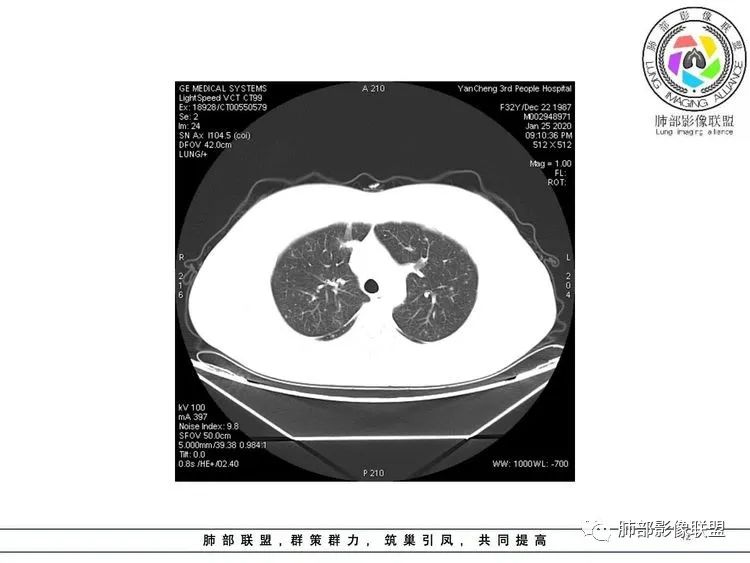

青年女性,急性发病。血象不高。

影像双肺多发大小不一结节,斑片实变,相应支气管管壁增厚。结节分布气道和血道均有,结节部分边缘不清,部分清,平直。考虑1感染性病变,亚急性播散性结核,结节大小不一,斑片实变共存,分布三不均匀,需要考虑;真菌,气道壁增厚,多发结节,需要免疫基础,结节缺乏晕征,暂不考虑;细菌性血播,不是以胸膜下为主,结节过多,需要结合临床。2非感染性炎症,血管炎?结节太多,太小,缺乏空洞。3肿瘤性病变,转移瘤,血道分布特点,结节光滑,恶性肿瘤不是,暂不考虑;血管内皮瘤,多发结节,血道、点晕,影像不支持。建议结合实验室检查,增强看看实变强化特点,纤支镜盥洗。

1.青年女性,发热咳嗽三天入院,病程短,血象不高。 医学百科网 | YxBaike.Com

2.双肺多发斑片影及结节影,部分密度较淡为磨玻璃。部分微小结节影高密度且边界清楚。 医学百科网 | YxBaike.Com

病灶分布不符合常见的细菌感染。 医学百科网 | YxBaike.Com

3.有老师分析出疱疹病毒感染,事实上患者也确实有“水痘”这个至关重要病史!诊断当无异议。